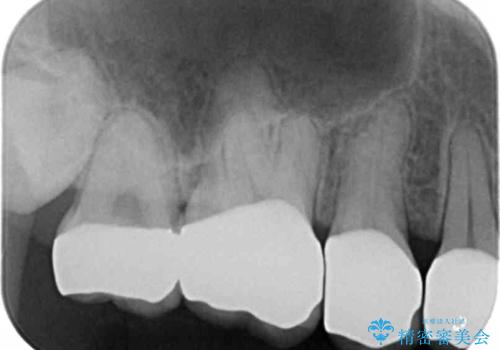

綺麗な仕上がりにご満足下さいました。

奥歯の咬み合わせも良くなったと喜んで頂けました。

患者様の理想とする韓流アイドルの写真を技工士さんに送り、最終的なクラウンの形や色をできるだけ理想に近づけられるよう努めました。

下顎はホワイトニングを行っております。

クラウンの種類:オールセラミッククラウン スタンダード